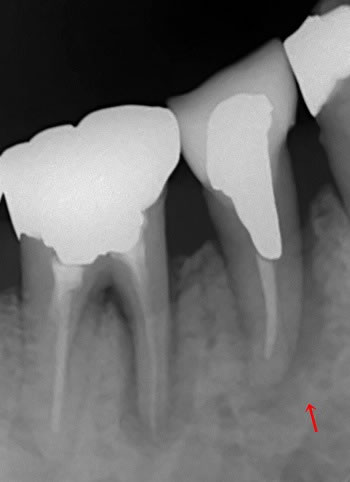

んんん、、、??? 赤い矢印ですが亀裂(クラック)かも???

根の治療が悪くて根尖病巣の場合は根の先に限局的ですが、亀裂を中心に根の周りの骨全体がぼんやりと黒くも見えますよね!!!

それともう一つ後ろの歯の前足も根の周りの骨が黒い!汗!

これもか???

とりあえずお痛みのある赤い矢印の方の歯は冠を外してみる事になりましたが、、、 |